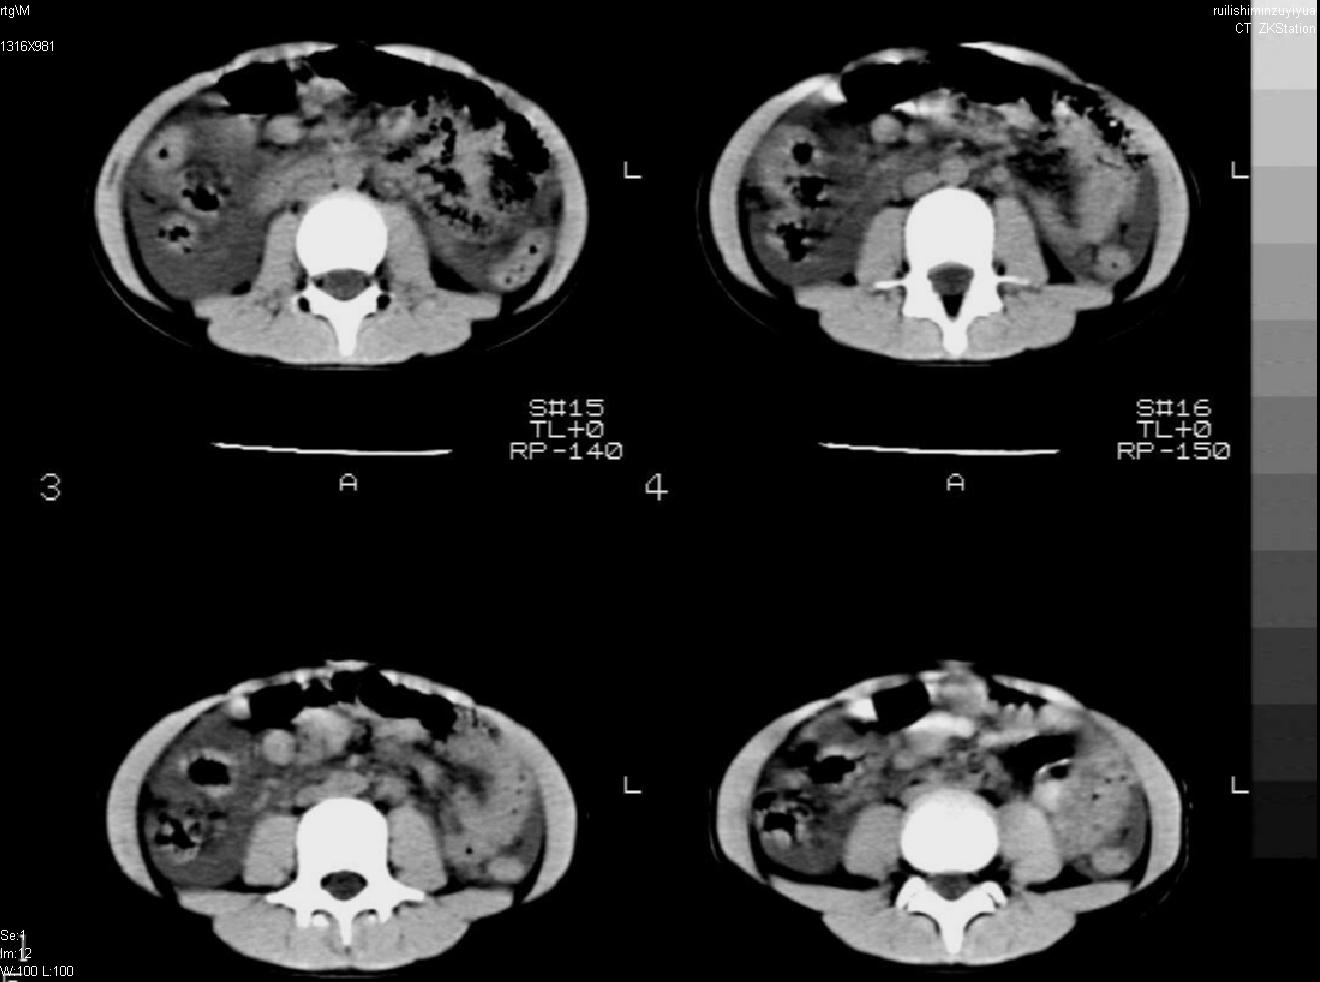

标题: PED0282:女,10岁,上腹疼痛2周 [打印本页]

标题: PED0282:女,10岁,上腹疼痛2周

b超:胆囊结石。疑坏死性胰腺炎

急性胰腺炎

考虑急性胰腺炎,胆道寄生虫。

考虑急性胰腺炎,

考虑急性胰腺炎

支持小儿急性坏死性胰腺炎。